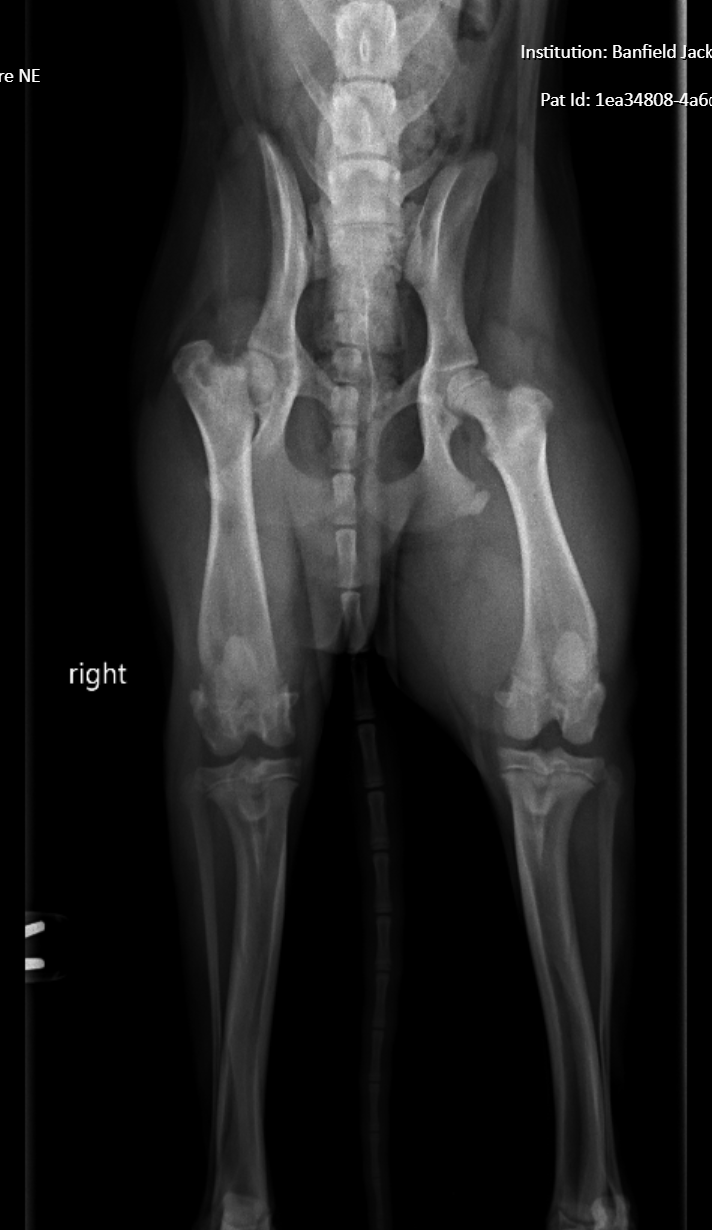

Noodle is my sweet puppy who recently suffered a serious injury to his back right hip, resulting in a displacement and fracture. The veterinarian has recommended FHO surgery to help him walk and play again, but the cost of the procedure is more than I can afford right now. Unfortunately, the payment plans available won’t cover the full amount. Noodle is scheduled for surgery tomorrow, and I’m doing everything I can to make sure he gets the care he needs.